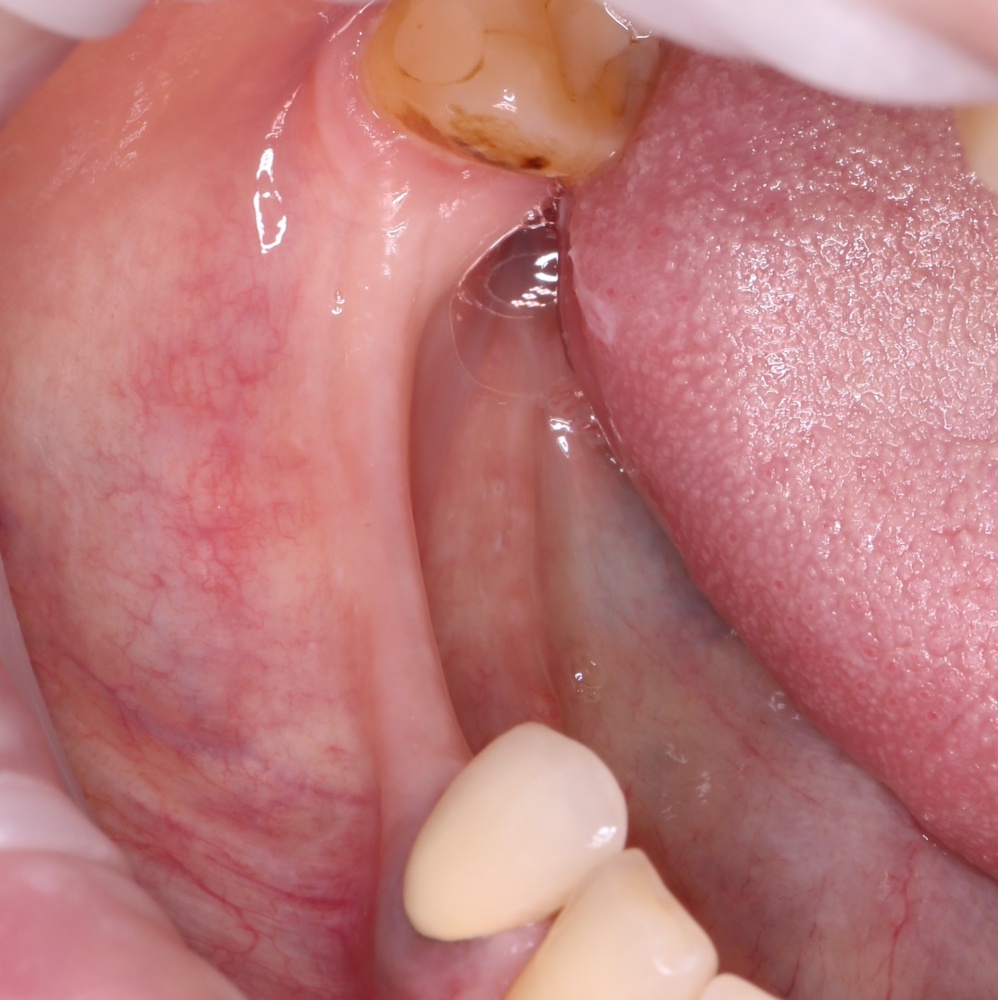

Вот клиническая картина через 4 месяца после ранее проведенной имплантации с остеопластикой:

Как видишь, коллеги из недалекой дружественной страны не осилили снятие швов. Мне это не нравится, хотя и объясняет, почему люди готовы ехать за тыщи километров ради 20-минутной операции удаления зуба мудрости.

Ну хорошо. Швы сняли. Делаем разрез. Обрати внимание, что после всех проведенных операций у нас остается очень небольшой по ширине слой жевательной слизистой оболочки: